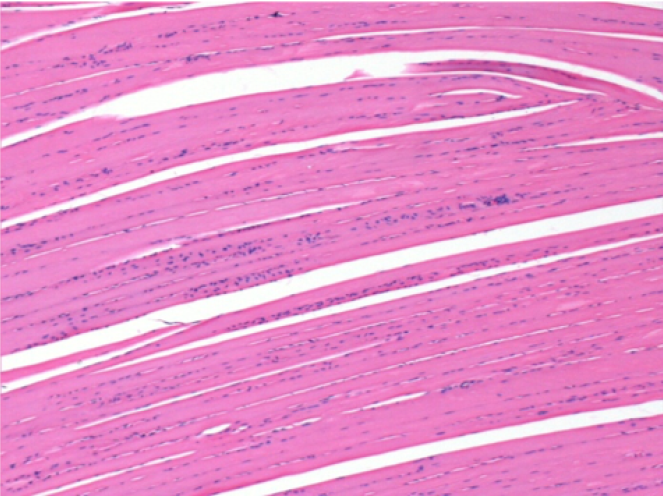

3 months (D90)after Endopeel Injection 0.1ml in the right pretibial muscle.

7 months (D210)after Endopeel IM Injection 0.1ml in the right pretibial muscle.

Complete Restitutio ad integrum after 7 months